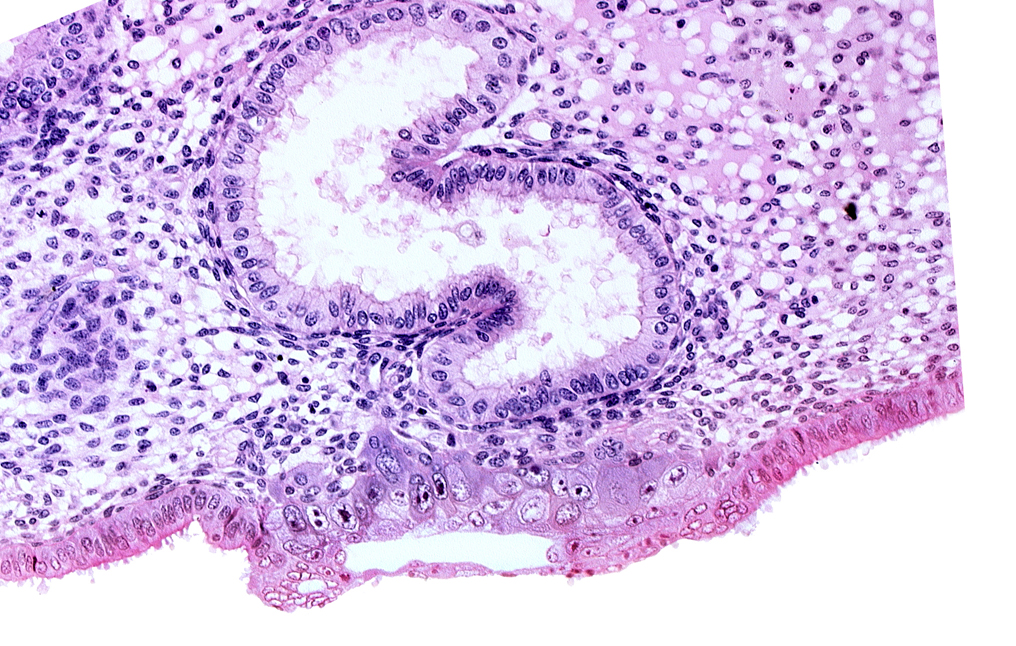

Carnegie Embryo #8020 | Location: 06-03-09

Keywords: blastocystic cavity (blastocoele), cytotrophoblast, edematous endometrial stroma (decidua), endometrial sinusoid, solid syncytiotrophoblast, syncytiotrophoblast / decidua interface, trophoblast, uterine cavity

Source: The Virtual Human Embryo.